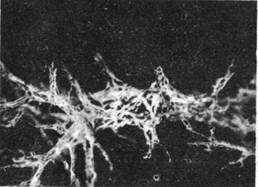

Рис. 1.4. Периваскулярные лимфатические сосуды паренхимы печени.

Кровоснабжение печени осуществляется ветвями собственной печеночной артерии. Кроме того, в печень поступает венозная кровь из воротной вены. Венозная кровь из паренхимы печени смешивается с кровью воротной вены и вместе с последней оттекает через печеночные вены и нижнюю полую вену. Лимфатических капилляров внутри долек печени нет, они сосредоточены в периваскулярной фиброзной капсуле как внутри, так и на поверхности органа (рис.1.3,1.4). Отводящие лимфатические сосуды следуют к печеночным, чревным, правым желудочным, диафрагмальным и задним медиастинальным лимфатическим узлам. Иннервация печени и желчных путей осуществляется ветвями печеночного сплетения (блуждающие и диафрагмальные нервы, симпатический ствол).